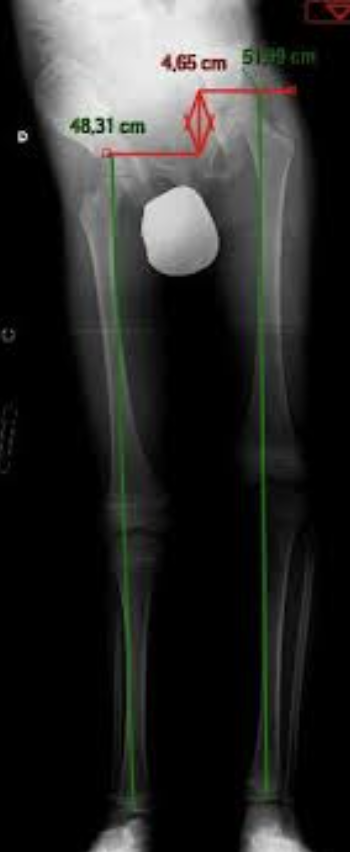

Imagerie : standard pour quantifier l’anatomique

Radiographie plein membre debout en charge

La télémétrie classique (radiographie plein membre debout)

Avant la diffusion du système EOS, la télémétrie plein membre debout en charge était la méthode standard pour évaluer une inégalité de longueur des membres inférieurs.

Elle reste aujourd’hui très répandue en France.

Principe

• Radiographie antéro-postérieure (AP) des deux membres inférieurs

• Patient debout, en charge bipodale

• Mesure de la distance entre repères osseux (tête fémorale → interligne tibio-talienne ou malléole)

Elle permet d’évaluer :

• longueur fémorale

• longueur tibiale

• ILMI totale

• alignement frontal (axe mécanique)

Précision et validité

Les études comparant la télémétrie debout au scanogramme (méthode CT de référence historique) montrent :

• corrélation élevée (r ≈ 0,96)

• reproductibilité excellente

• différence moyenne entre méthodes ≈ 5 mm

• limites d’accord pouvant atteindre ± 10–15 mm chez certains individus

(Sabharwal 2006 ; Cleveland 1988)